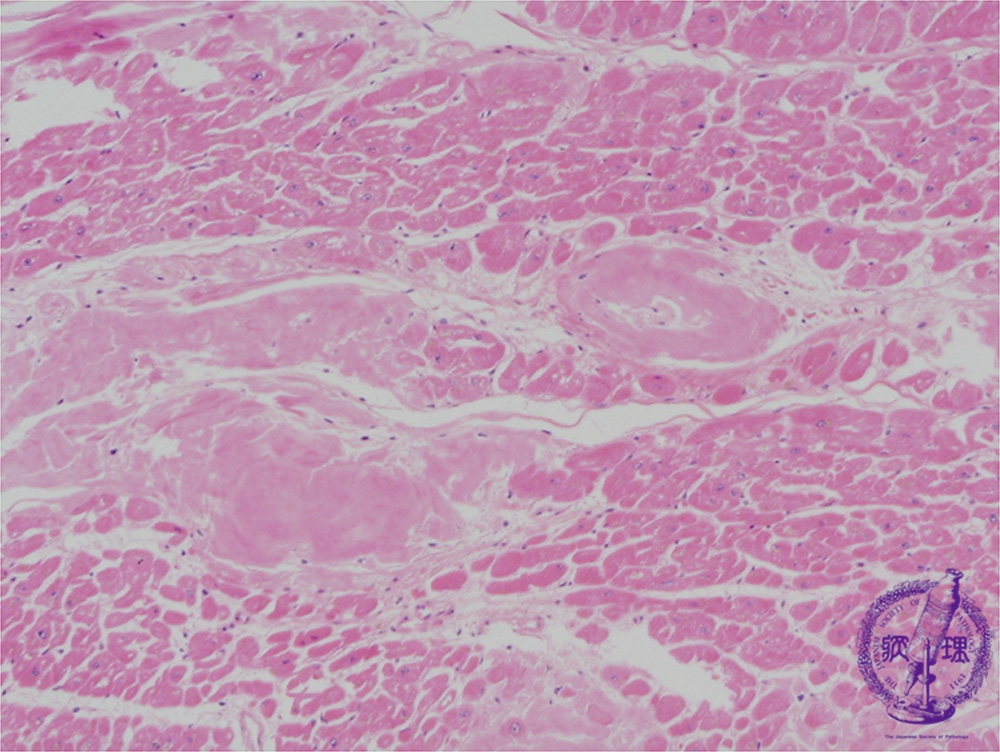

Microscopic image (HE, low power view): Perivascular or perimyocyte interstitial deposition of an eosinophilic, amorphous substance (amyloid).